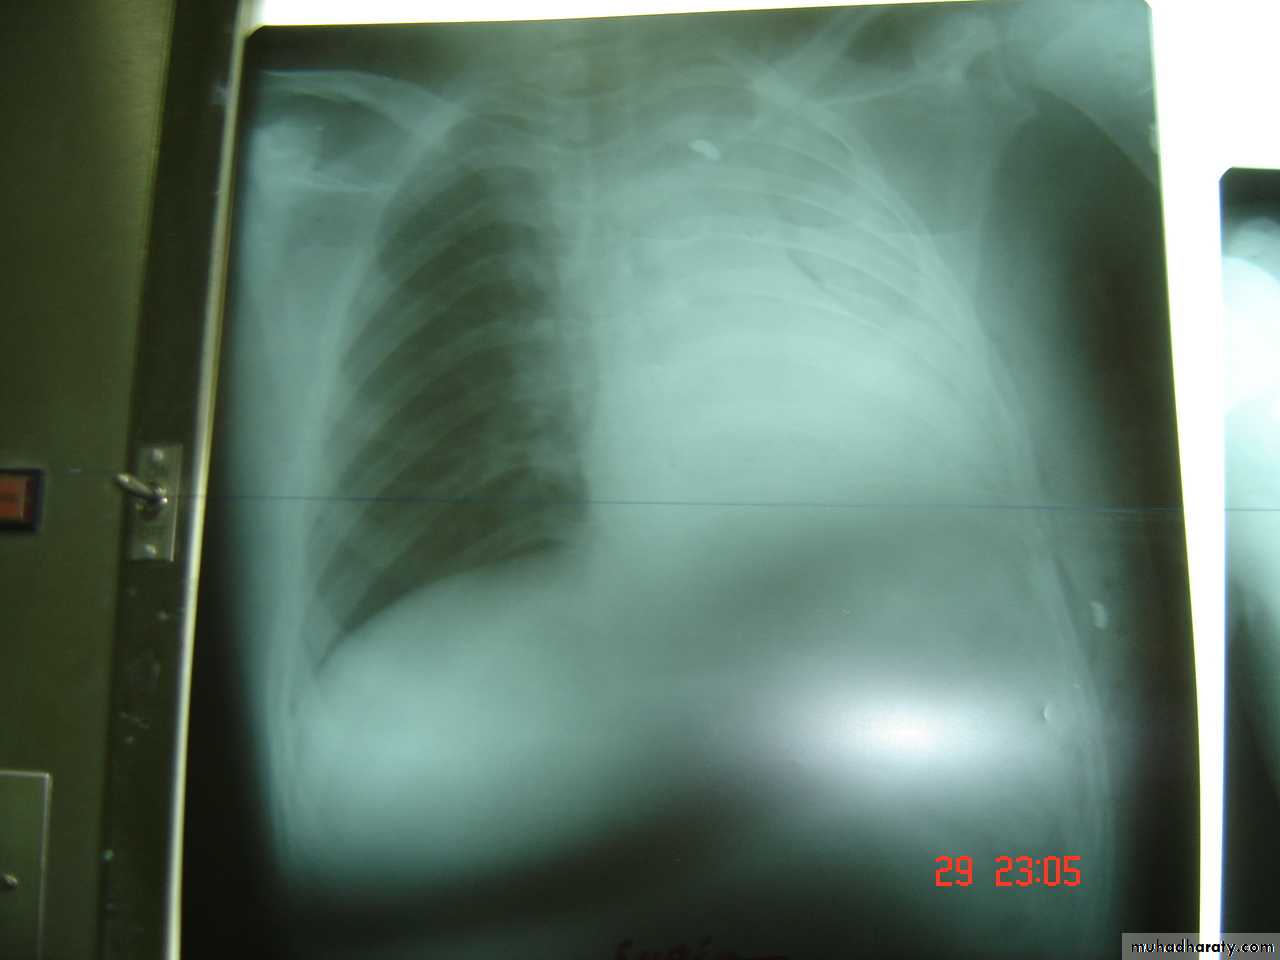

Is the accumulation of air inside the pleural cavity , occurring without any known etiology .More in males ,more on the right side .It can be bilateral

• Causes 1- Ruptured pulmonary bleb.2-Ruptured of a cystic defect in the pleura.3-Teared visceral pleura 4-No cause can be demonstrated in (15-20%).Complications:-1-pleural effusion2-empyema 3-tension pneumothorax which leads to mediastinal shift &circulatory collapse.4-Respiratory failure in elderly patient with COAD .

• 4-Pleural effusion

• Is the accumulation of fluid in the pleural space excessive transudation or exudation of the interstitial fluid from the pleural surface. It is signfrom ify pleural or systemic disease .

• Its effect depends on its size (mild , moderate or massive ) & the state of the underlying lung .It is classified as transudate when the protein content is less than 3g/100ml, or exudates when protein content is more than 3 gm /100ml.Clinically patients will present with dyspnea & pleuritic chest pain

• Radio logically (concave meniscus sign)